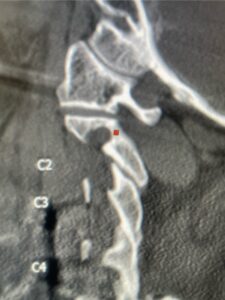

Fig 2: Sagittal cervical CT pyelogram demonstrating a very narrow C 2 pars and prominent vertebral foramen making in unsafe to place a pars screw

Patient had an existing peripheral occipital nerve stimulator and therefore we had ordered a myelogram since it was not MRI compatible. The patient underwent a decompressive laminectomy and in situ fusion at C2-3. Care was made to preserve a good portion of the C2-3 facets bilaterally. It was felt that her C2 pars anatomically were not favorable to accept pars screws given the proximity of the vertebral foramen with a resultant narrow par (Fig. 2). She also had a normal C2-3 vertebral alignment. Post-operatively she had improvement of her arm pain and strength in right arm. In this case we made a decision to decompress the patient posteriorly given her prior anterior surgery, a more difficult approach to C23 disc space, and significant C23 disc collapse. A posterior approach was favorable in our opinion given the prior posterior surgery was more inferior with less scarring likely to be encountered in the C1-3 region. A posterior decompression also can yield a more adequate spinal cord decompression. Since we elected not to place pars screws because of her anatomy, and perform an in-situ fusion, careful attention was made to preserve as much of the C23 facet complex as possible.